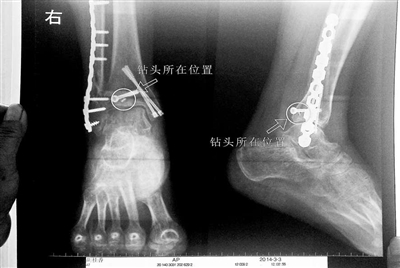

胡女士的腿部X光圖

看著X光片中自己腿內(nèi)的異物,胡女士就感到莫名的擔(dān)憂。胡女士于2013年3月在北京市豐臺區(qū)右安門醫(yī)院進行了一次骨折手術(shù),術(shù)后醫(yī)生才發(fā)現(xiàn)手術(shù)時用來打眼用的鉆頭不慎遺留在了胡女士的骨頭中,并且無法取出。

近日,在豐臺區(qū)右安門醫(yī)院,北京青年報記者見到了胡女士,她走起路來顯得一瘸一拐,腿腳并不利索。在她帶來的X光片上,可以清晰地看到,有一個異物存在于腿內(nèi)部。

“我當(dāng)時就嚇蒙了,怎么會有一個鉆頭在骨頭里?”胡女士余悸未消地說,第二天拍攝的X光片顯示,2厘米左右的鉆頭遺留在她右腳腳踝上部的骨頭內(nèi)。

胡女士說,當(dāng)時旁邊的醫(yī)生勸慰自己,稱鉆頭留在腿里并不會有什么問題。出院后,胡女士每個月都會來醫(yī)院做復(fù)查,拍X光片。她說,每次都能夠清晰地看見自己骨頭里的那個明晃晃的“小東西”。